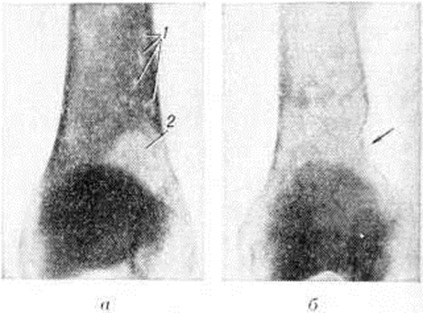

Множественно-очаговая форма встречается более чем в 70% случаев, рентгенологически характеризуется образованием множественных округлых дефектов диаметром до нескольких сантиметров. Изменения выявляются чаще всего в плоских костях (рисунок 9), реже — в длинных и коротких трубчатых. Каждый дефект чётко контурирован, реактивных изменений со стороны окружающей ткани при этом нет. В трубчатых костях корковое вещество изнутри истончается, костномозговая полость расширяется, на месте наиболее крупных узлов кость слегка вздувается и утолщается (рисунок 10, а). В ряде случаев может наблюдаться полное разрушение коркового вещества кости (рисунок 10, б) с распространением опухоли в мягкие ткани. Характерная картина выявляется при поражении костей черепа, в котором видны множественные, словно выбитые пробойником, дефекты кости (рисунок 11). В позвоночнике обнаруживается диффузное разрежение костной структуры, уплощение тел позвонков (бревиспондилия, «рыбьи позвонки»), искривление позвоночного столба. На фоне диффузного разрежения костного вещества тел позвонков заметна подчёркнутость дужек и отростков позвонков, что, как правило, отсутствует при метастатических поражениях позвоночника.